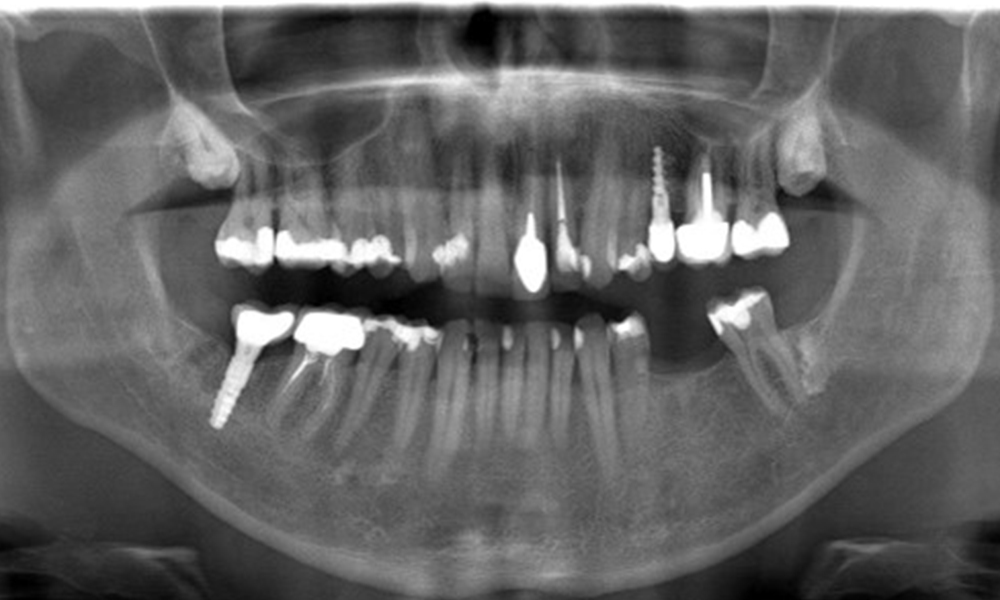

In the medical history, the 55-year-old patient states that he has no systemic disease and is not taking any medication. The patient’s lifestyle is similarly unremarkable. The patient has a few tooth restorations and two implants (2nd and 4th quadrants). On the basis of current findings, gingivitis is identified in an otherwise stable periodontal condition on the reduced periodontium (stage III, grade A).

Previous treatments: dental restorations (non-precious metal/ceramic blend), two implants (2nd, 4th quadrants)